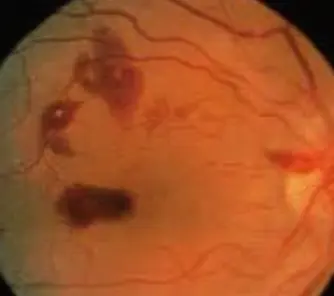

Cherry red spot

Scenario VSD, did dental, didnt get antibiotics

Findings Roth spots